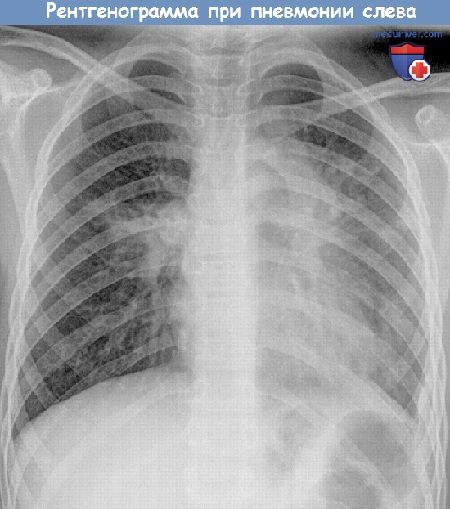

Для диагностики пневмонии врач прослушивает дыхание ребенка стетоскопом, дает направление на сдачу анализа крови и прохождение рентгента грудной клетки. При пневмонии прослушиваются хрипы влажные и мелкопузырчатые, а при бронхите они сухие и свистящие. В последнее время для точной постановки диагноза “пневмония” терапевты используют результаты анализа крови на С реактивный белок.

По результатам такого исследования можно определить, насколько сильно воспаление в легких. Если уровень С реактивного белка меньше 20 мг/л, то, скорее всего, у ребенка – бронхит, а воспаления в легких нет. Если же этот показатель приближается к 100 мг/л, то надо срочно сделать рентгеновский снимок, чтобы окончательно подтвердить диагноз “пневмония”.

- рентгенограммы легких;

- Рентгенография органов грудной полости.